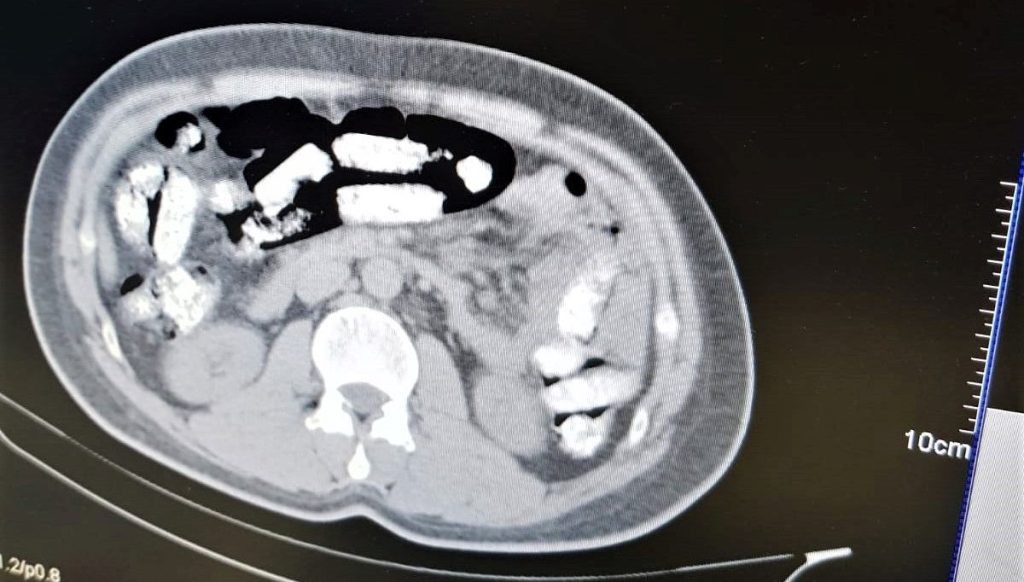

İran otobüsünde seyahat yapan Abdulmennan S. isimli İran asıllı kişinin yutma usulüyle uyuşturucu taşıdığı kıymetlendirilmesi üzerine, Erzincan Mengücek Gazi Eğitim ve Araştırma Hastanesinde zanlının vücudundan 106 fişek halinde toplamda 1 kilo 198 gram Afyon Sakızı ele geçirildi.